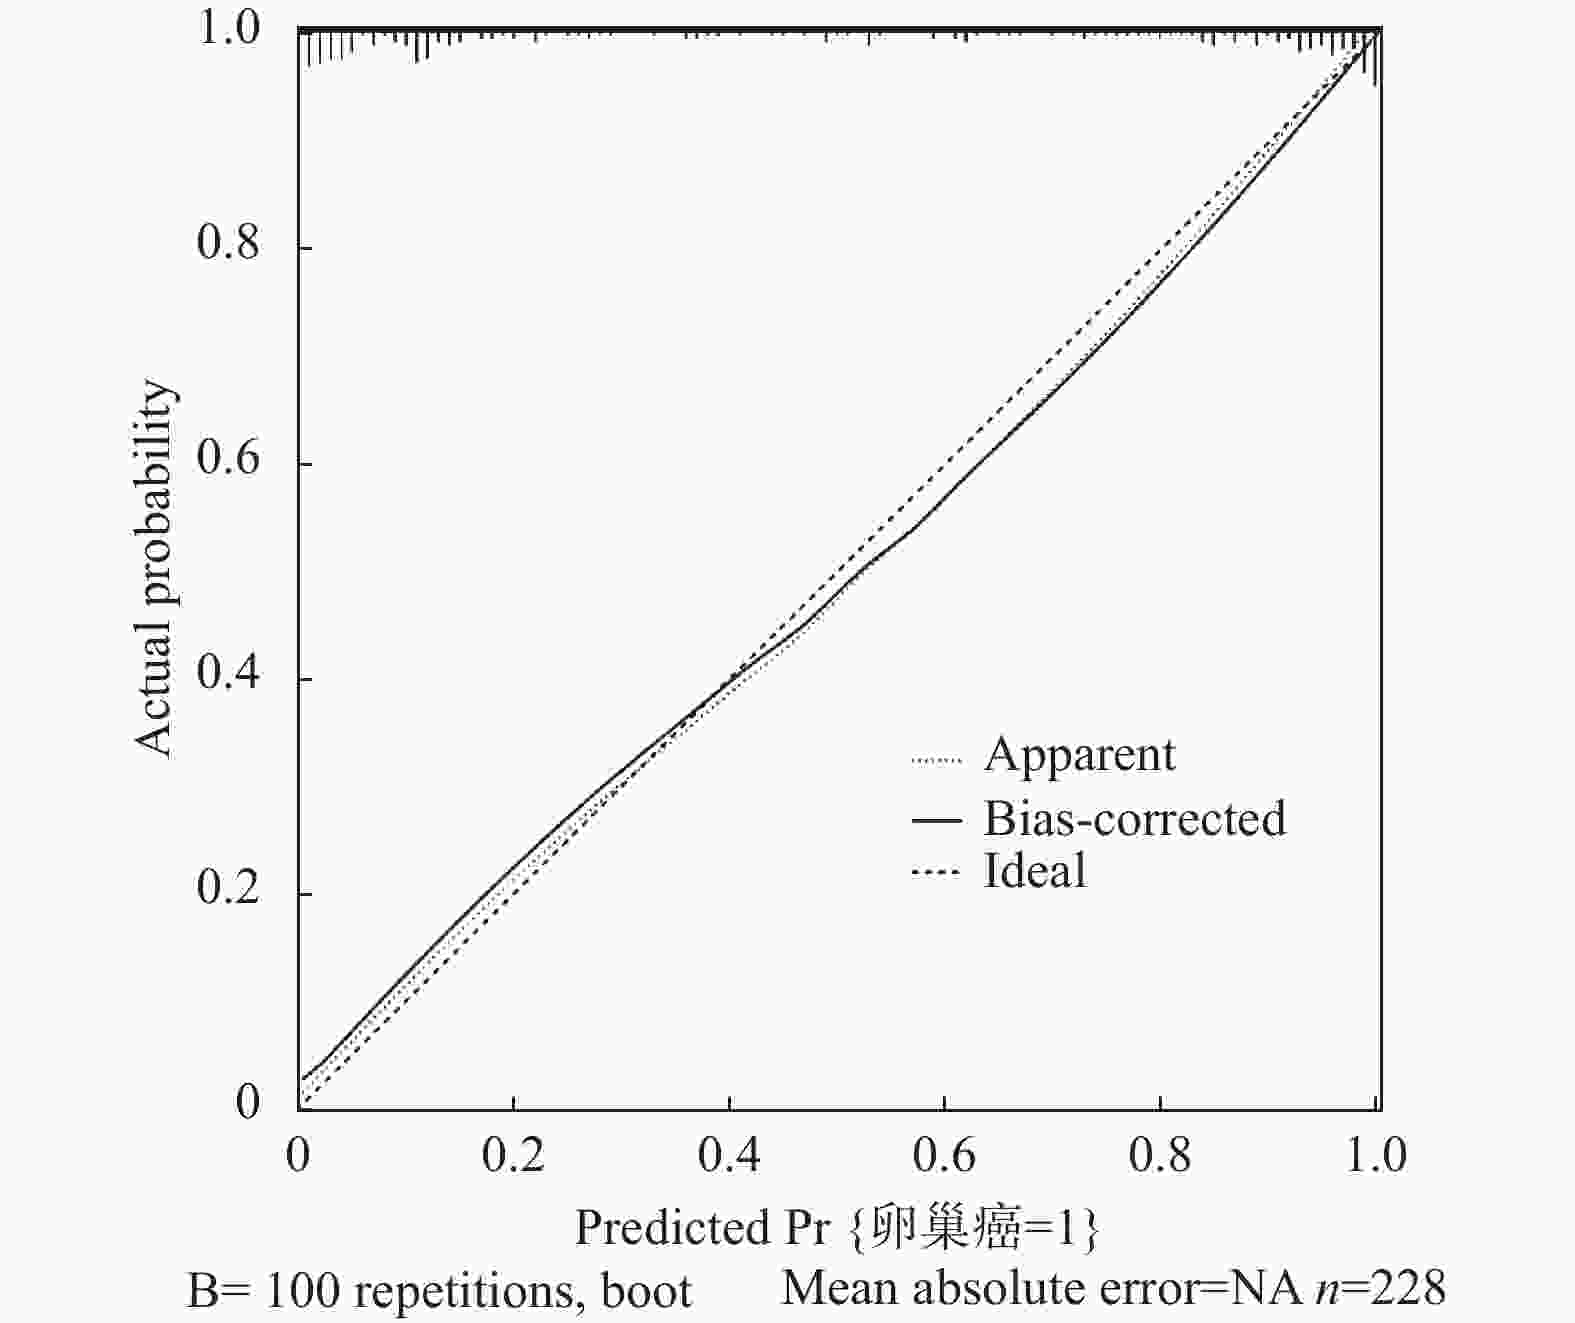

目的 探究超声联合血清白细胞介素-1β(interleukin-1β,IL-1β)、C角蛋白19片段抗原21-1(cytokeratin 19 fragment antigen 21-1,CYFRA21-1)对卵巢癌的诊断价值。 方法 于2020年7月至2023年7月选取沧州中西医结合医院收治的卵巢肿瘤患者250例,经病理检测确诊为卵巢癌的患者114例即为卵巢癌组,从136例良性肿瘤患者中随机选择114例卵巢良性病变患者即为对照组。采用彩色超声诊断仪对所有研究对象进行诊断。采用酶联免疫吸附(enzyme linked immunosorbent assay,ELISA)法检测血清中IL-1β、CYFRA21-1水平。Kappa检验分析诊断方法与手术病理结果的一致性。多因素Logistic回归分析卵巢癌发生影响因素。受试者工作特征(receiver operating characteristic,ROC)曲线分析超声联合血清IL-1β、CYFRA21-1对卵巢癌的诊断价值。 结果 卵巢癌组患者血清中IL-1β、CYFRA21-1水平与对照组相比显著升高(P < 0.05)。与透明细胞癌相比,粘液性腺癌和浆液性腺癌患者血清中IL-1β、CYFRA21-1水平依次显著升高(P < 0.05)。卵巢癌患者血清中IL-1β、CYFRA21-1水平在Ⅰ期<Ⅱ期<Ⅲ期<Ⅳ期(P < 0.05)。血清IL-1β、CYFRA21-1水平升高是卵巢癌发生的危险因素(P < 0.05)。超声联合血清IL-1β、CYFRA21-1对卵巢癌诊断的曲线下面积(area under the curve,AUC)显著高于单一指标诊断的AUC值(Z超声~超声+IL-1β+CYFRA21-1=3.782,P < 0.001;ZIL-1β~超声+IL-1β+CYFRA21-1=4.046,P < 0.001;ZCYFRA21-1~超声+IL-1β+CYFRA21-1=7.279,P < 0.001)。以病理检查结果为依据,联合诊断的一致性(Kappa值=0.789)高于超声(Kappa值=0.658)单独诊断。 结论 超声联合血清IL-1β、CYFRA21-1对卵巢癌的诊断效能较高。 -

Abstract:Objective To explore the diagnostic value of ultrasound combined with serum interleukin-1β (IL-1β) and cytokeratin 19 fragment antigen 21-1 (CYFRA21-1) in ovarian cancer. Methods From July 2020 to July 2023, 250 patients with ovarian tumors admitted to Cangzhou Integrated Chinese and Western Medicine Hospital were enrolled. Among them, 114 patients confirmed as having ovarian cancer by pathological examination comprised the ovarian cancer group. Additionally, 114 patients were randomly selected from the remaining 136 patients with benign tumors to form the control group. All study subjects underwent diagnosis using color ultrasound diagnostic equipment. Serum levels of IL-1β and CYFRA21-1 were detected using the enzyme linked immunosorbent assay (ELISA) method. Kappa test was used to analyze the consistency between diagnostic methods and surgical pathological results. Multivariate logistic regression analysis was performed to identify risk factors for ovarian cancer occurrence. Receiver operating characteristic (ROC) curve analysis was used to evaluate the diagnostic value of ultrasound combined with serum IL-1β and CYFRA21-1 for ovarian cancer. Results Serum levels of IL-1β and CYFRA21-1 in the ovarian cancer group were significantly elevated compared to the control group (P < 0.05). Compared with clear cell carcinoma, serum levels of IL-1β and CYFRA21-1 in patients with mucinous adenocarcinoma and serous adenocarcinoma were significantly elevated (P < 0.05). Serum levels of IL-1β and CYFRA21-1 in ovarian cancer patients showed a progressive increase across stages I<stage II<stage III<stage IV (P < 0.05). Elevated serum levels of IL-1 β and CYFRA21-1 were risk factors for ovarian cancer (P < 0.05). The area under the curve (AUC) for the combined ultrasound with serum IL-1β and CYFRA21-1 in diagnosing ovarian cancer was significantly higher than the AUC values of single-indicator diagnosis (Zultrasound~ultrasound+IL-1β+CYFRA21-1=3.782, P < 0.001; ZIL-1β~ultrasound+IL-1β+CYFRA21-1=4.046, P < 0.001; ZCYFRA21-1~ultrasound+IL-1β+CYFRA21-1=7.279, P < 0.001). Based on pathological examination results, the consistency of combined diagnosis (Kappa value=0.789) was higher than ultrasound alone (Kappa value=0.658). Conclusion The combined diagnostic approach of ultrasound with serum IL-1β and CYFRA21-1 demonstrates high diagnostic efficacy for ovarian cancer. -